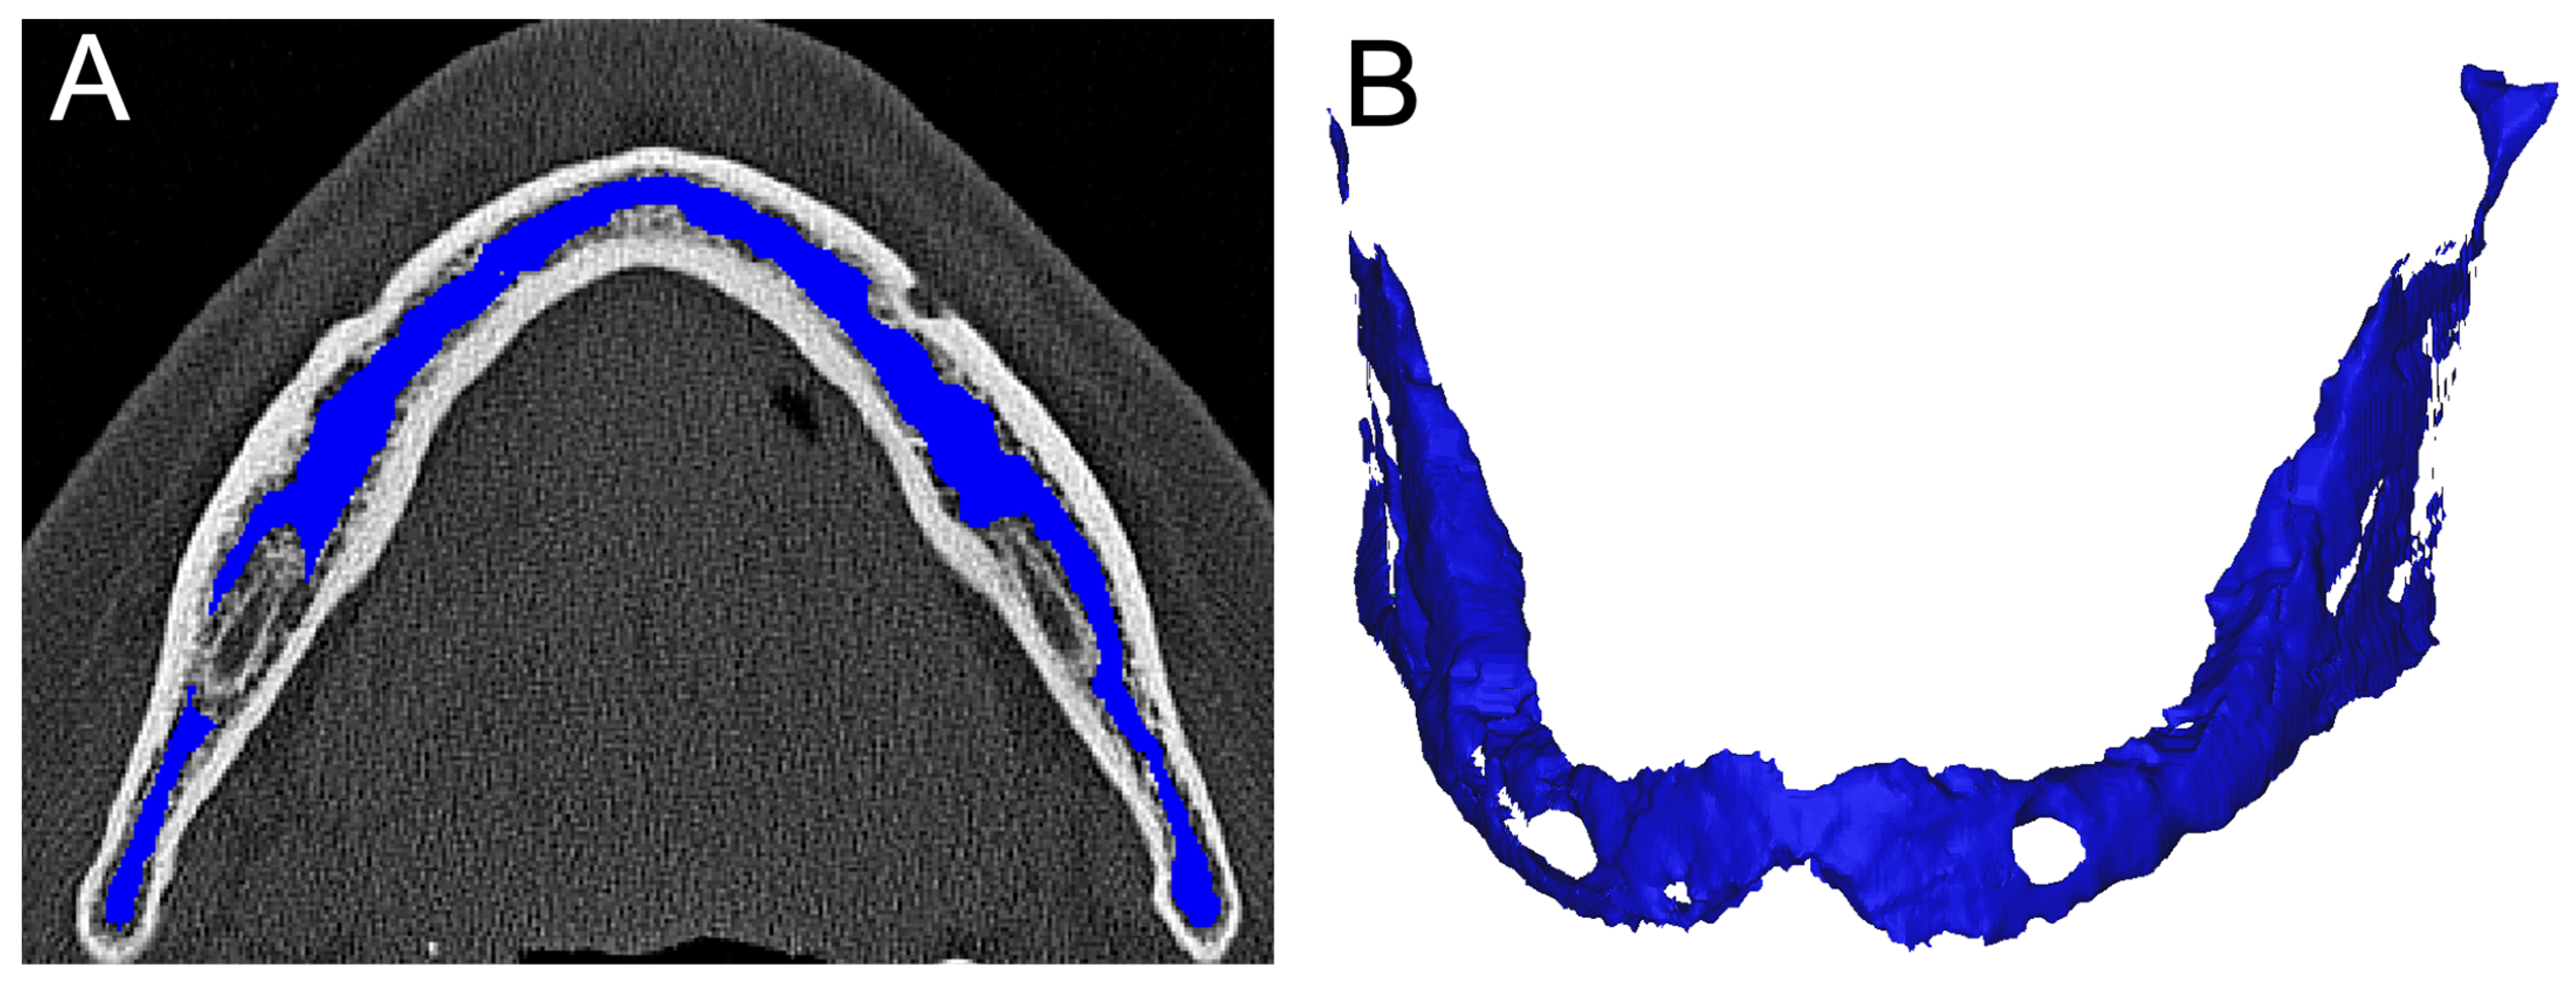

2.4. Image Analysis and Segmentation

2.6. Segmentation